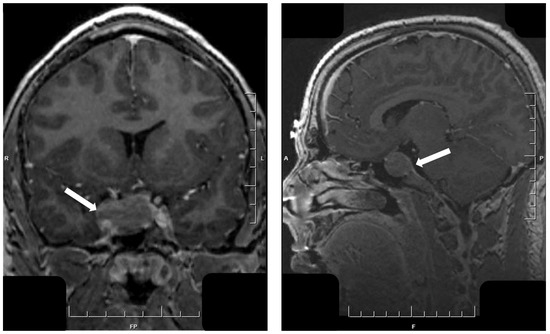

- Asa, S.L.; Kucharczyk, W.; Ezzat, S. Pituitary acromegaly: Not one disease. Endocr. Relat. Cancer 2017, 24, C1–C4. [Google Scholar] [CrossRef] [PubMed]

- Heck, A.; Ringstad, G.; Fougner, S.L.; Casar-Borota, O.; Nome, T.; Ramm-Pettersen, J.; Bollerslev, J. Intensity of pituitary adenoma on T2-weighted magnetic resonance imaging predicts the response to octreotide treatment in newly diagnosed acromegaly. Clin. Endocrinol. (Oxf.) 2012, 77, 72–78. [Google Scholar] [CrossRef]

- Hagiwara, A.; Inoue, Y.; Wakasa, K.; Haba, T.; Tashiro, T.; Miyamoto, T. Comparison of growth hormone-producing and non-growth hormone-producing pituitary adenomas: Imaging characteristics and pathologic correlation. Radiology 2003, 228, 533–538. [Google Scholar] [CrossRef] [PubMed]

- Potorac, I.; Petrossians, P.; Daly, A.F.; Alexopoulou, O.; Borot, S.; Sahnoun-Fathallah, M.; Castinetti, F.; Devuyst, F.; Jaffrain-Rea, M.L.; Briet, C.; et al. T2-weighted MRI signal predicts hormone and tumor responses to somatostatin analogs in acromegaly. Endocr. Relat. Cancer 2016, 23, 871–881. [Google Scholar] [CrossRef] [PubMed]